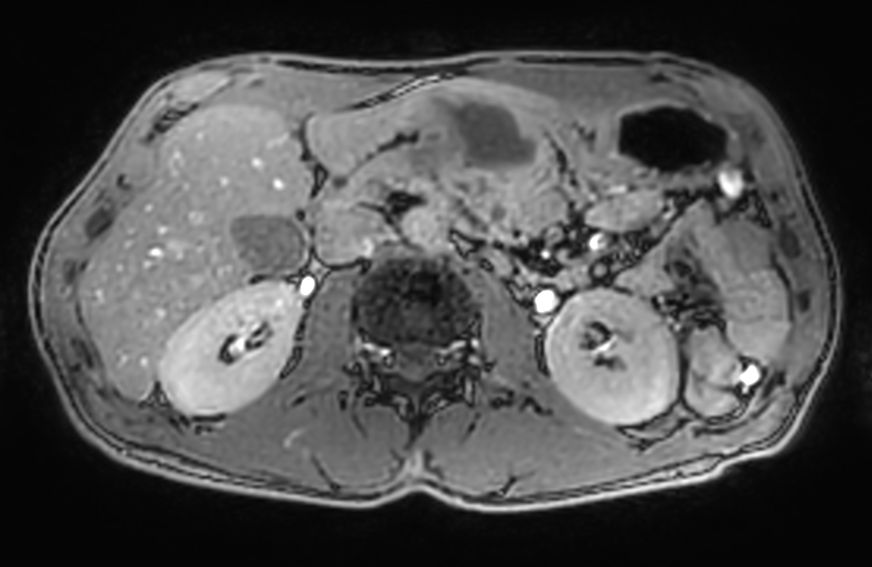

Axial T2w TSE MultiVane XD